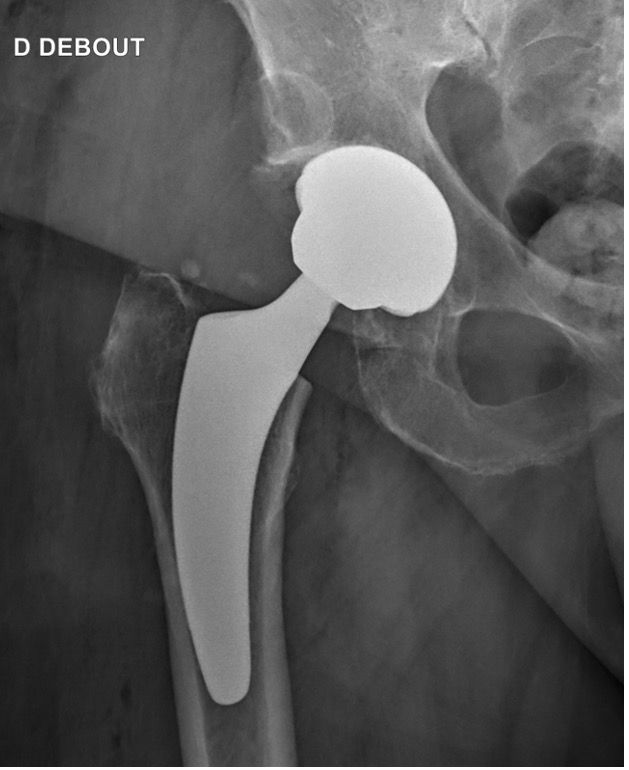

Hips in coxa vara sometimes present a very significant femoral offset which may be prove to be difficult to restore using standard stems. In this case, a varus-tilted or lateralized stem should be used and this will require a very low femoral cut, often with loss of residual femoral offset and a risk of lengthening the lower limb. Positioning a straight cementless stem in varus runs the risk of trajectory error and femoral pain. If a modular neck implant is chosen, the increased lever arm results in significant pressures on the modular neck and neck-head junction with risks that are already known. Finally, even with a cemented stem, positioning it in varus will increase the pressures on the bone-cement interface, with a risk of early loosening. With calcar-guided short stems, the stem will follow the medial cortex of the neck (which will have been cut high), naturally finding a varus tilt and making it possible to reproduce even very significant offsets (Figs 4 and 5).

In total hip replacement, there is often a relative reduction in the acetabular offset due to burring off a few millimetres, which is necessary for the implant to fit in the hip socket cavity, and this is compensated for by a relative increase in femoral offset, to restore the overall hip offset.